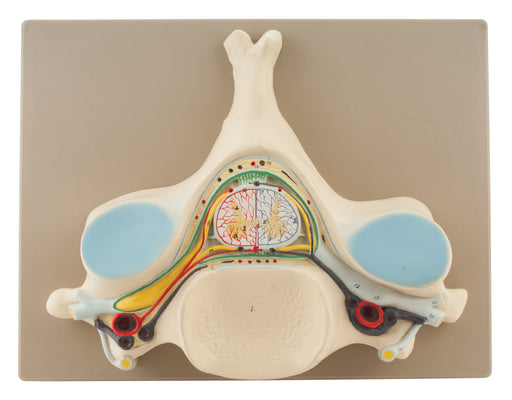

5th Vertebrae

This model is enlarged approx 8 times and showing the detailed structure of the 5 th cervical vertebrae, a transverse of the spinal cord with gey a...